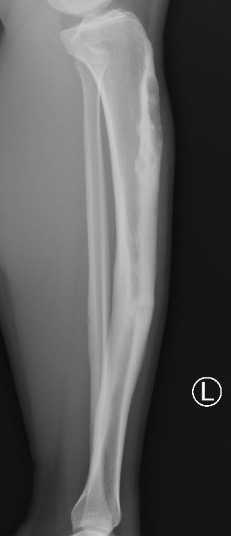

Osteofibrous DysplasiaAdamantinomaEwings

OFD                    Adamantinoma                                Ewings

• Diaphyseal lesions